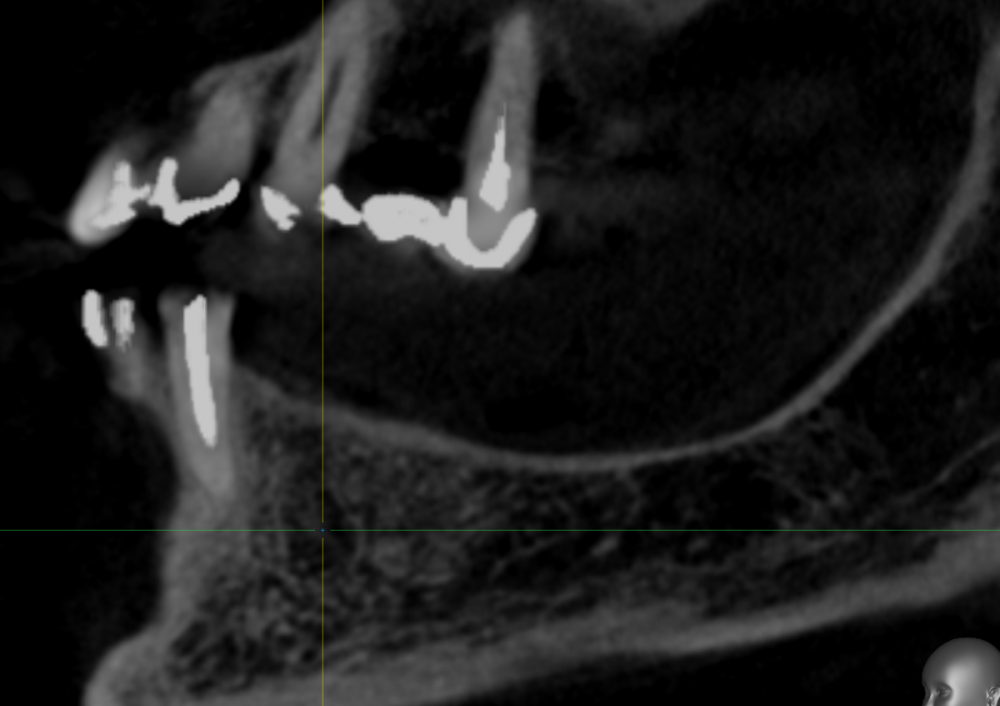

It'sGeorgy Опубликовано 15 мая, 2021 Автор Поделиться Опубликовано 15 мая, 2021 Пациент пропал на год, позвонил в клинику сегодня, отправили на кт. Сказал, на десне какой-то прыщик на десне(скорее всего, причина в этой оставленной штуки в десне) и что-то где-то там болит(сверху пульпит прям над винтом). В прошлых сообщениях забыл указать: графта не было. А вот имплантат откровенно неудачно поставил, надеюсь, десна вывезет. Да и сам имплантат, если бы сейчас ставил, выбрал Штрауманн ТЛ. 1 Ссылка на комментарий

It'sGeorgy Опубликовано 15 мая, 2021 Автор Поделиться Опубликовано 15 мая, 2021 Только что, Irouil сказал: А что,собственно, не нравится? ну язычнее надо бы...вестибулярная стенка у шейки совсем тонкая. Ну и десны после транспа с бугра много вышло, 5.5 мм по КТ(знаю, что это не всегда соответствует реальности, но все же). В таких случаях стараюсь полированной шейкой поддесневую часть выполнять, ибо любая недополировка абатмента или поддесневой части коронки будет критична. Ссылка на комментарий

Irouil Опубликовано 16 мая, 2021 Поделиться Опубликовано 16 мая, 2021 У вас по КТ и над зубами десны по пару мм. да и ничего плохого в 5 мм не было бы. Во первых, всегда можно использовать абатменты с высокой шейкой, а во вторых очень редко когда нельзя все это расформировать в широкий контур прорезывания временной коронкой. С костью все нормально, имхо 1 Ссылка на комментарий

It'sGeorgy Опубликовано 16 мая, 2021 Автор Поделиться Опубликовано 16 мая, 2021 6 часов назад, Irouil сказал: У вас по КТ и над зубами десны по пару мм. Таки да, не заметил посмотрим на этапе фдм что там с десной в итоге. 6 часов назад, Irouil сказал: а во вторых очень редко когда нельзя все это расформировать в широкий контур прорезывания временной коронкой. Обсудим этот момент с ортопедом, спасибо. Ссылка на комментарий